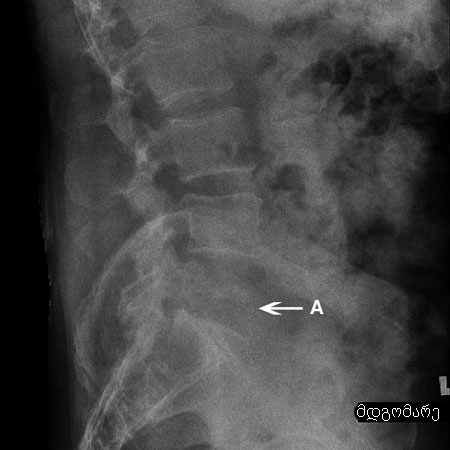

თუ კომპრესიული მოტეხილობა განვითარდა დაბალი ენერგიის მქონე მექანიზმით, უნდა ვეძებოთ მოტეხილობის მეტაბოლური მიზეზები. შემდგომი მოტეხილობების პრევენციისთვის საჭიროა ოსტეოპოროზის აგრესიული მკურნალობა.[Figure caption and citation for the preceding image starts]: კომპრესიული მოტეხილობის რენტგენი: ლატერალური პროექციის რენტგენი L2 კომპრესიული მოტეხილობის დროს (A). შეინიშნება მალის სხეულის სოლისებრი დეფორმაციაექიმ Dr K. Singh საკუთრება; გამოყენებულია ნებართვით [Citation ends].